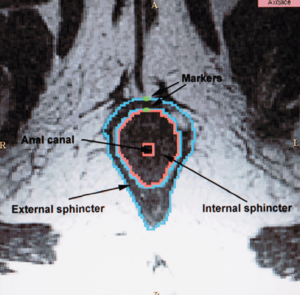

- 13.1 Magnetic Resonance Imaging and 3-Dimensional Analysis of External Anal Sphincter Anatomy

- 15.4 Three-dimensional Reconstruction of Magnetic Resonance Images of the Anal Sphincter and Correlation between Sphincter Volume and Pressure